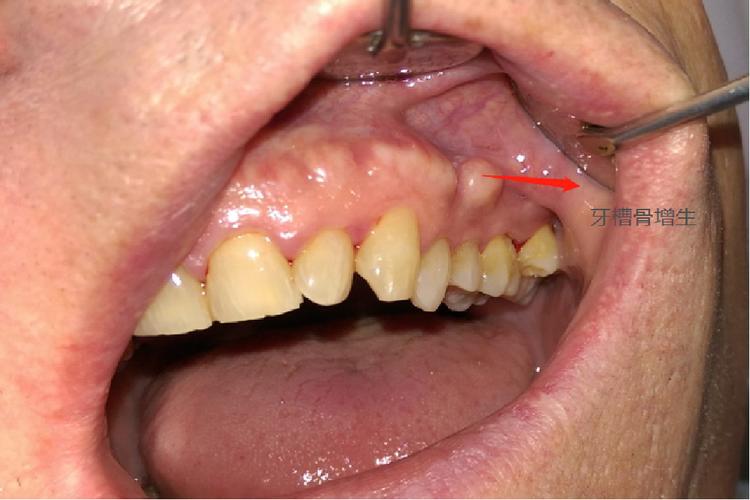

生理性牙槽骨增生通常无明显临床症状,通过影像学检查(如X光片、CBCT)可观察到牙槽骨形态逐渐规则,密度均匀升高,牙齿移动稳定,属于矫正过程中的正常现象,而病理性增生则可能带来一系列问题:

牙周组织损伤:病理性增生常伴随牙槽骨形态异常,如骨皮质增厚、牙槽嵴顶凸起,可能压迫牙龈组织,导致牙龈退缩、牙根暴露,或形成“骨刺”刺激牙龈,引发牙龈炎、牙周袋形成,影响牙周健康。